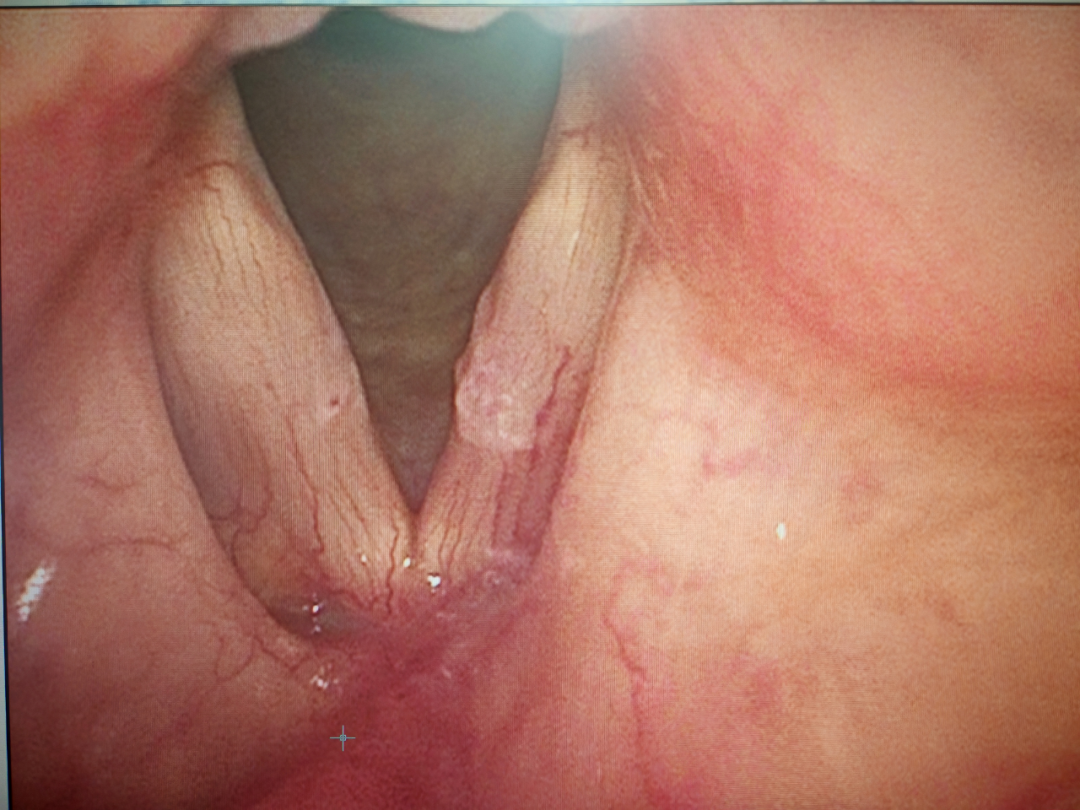

治疗前

图片

治疗后